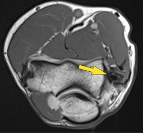

Axial:

![]() |